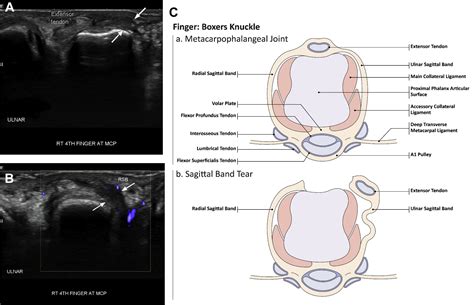

A sagittal band rupture refers to an injury to the sagittal bands, which are fibrous structures that stabilize the extensor tendons over the metacarpophalangeal (MCP) joints of the fingers. These bands are essential for maintaining the alignment and function of the extensor tendons, allowing for smooth and efficient finger movements. When these bands rupture, it can lead to a condition known as "extensor tendon subluxation," where the tendons slip out of their normal position, causing pain and functional impairment.

Diagnosing a sagittal band rupture involves a combination of physical examination and imaging studies. A healthcare provider will typically:

• Conduct a thorough physical examination, assessing the range of motion, strength, and stability of the affected finger.

• Order imaging studies, such as X-rays or MRI scans, to visualize the extent of the injury and rule out other potential causes of symptoms.

In some cases, a dynamic ultrasound may be used to observe the movement of the extensor tendons in real-time, providing valuable information for diagnosis and treatment planning.